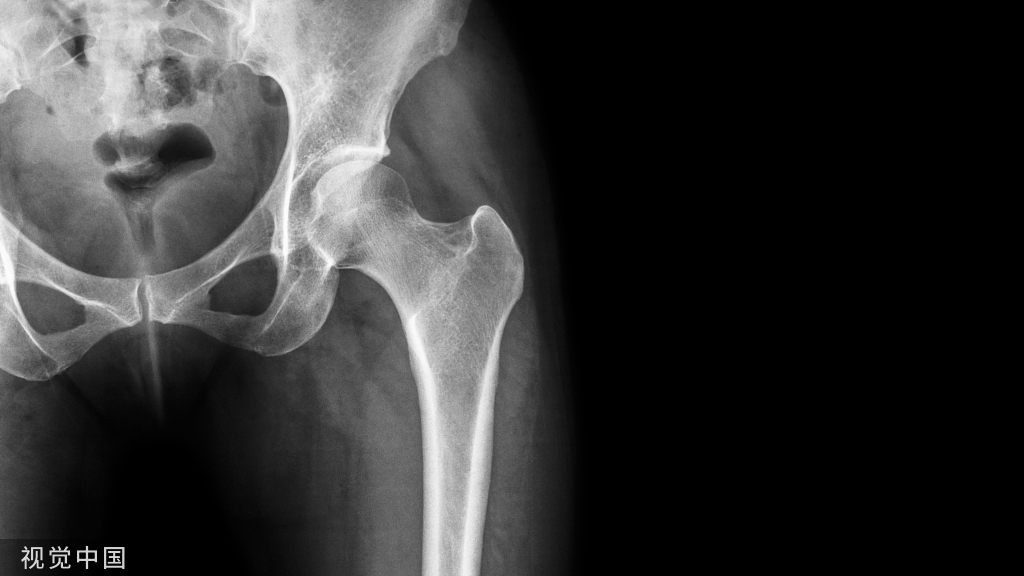

内生软骨瘤常见于10~30 岁青年人,多发于手足短管状骨,多在指骨和掌骨。发病部位局部红肿疼痛,软组织肿胀。边界清楚的髓腔内膨胀性骨质破坏,内见钙化病灶侵蚀骨皮质膨胀变薄。

破坏区内可见散在的砂粒样、点状、小环行钙化影;周缘呈花边或波浪状硬化边。钙化灶密度不均,形态不一,为软骨基质钙化程度不同,环弧状钙化具有特征性。病程缓慢,一般无明显症状,往往经数年后由于肿瘤长大发现,若生长迅速则提示恶变。